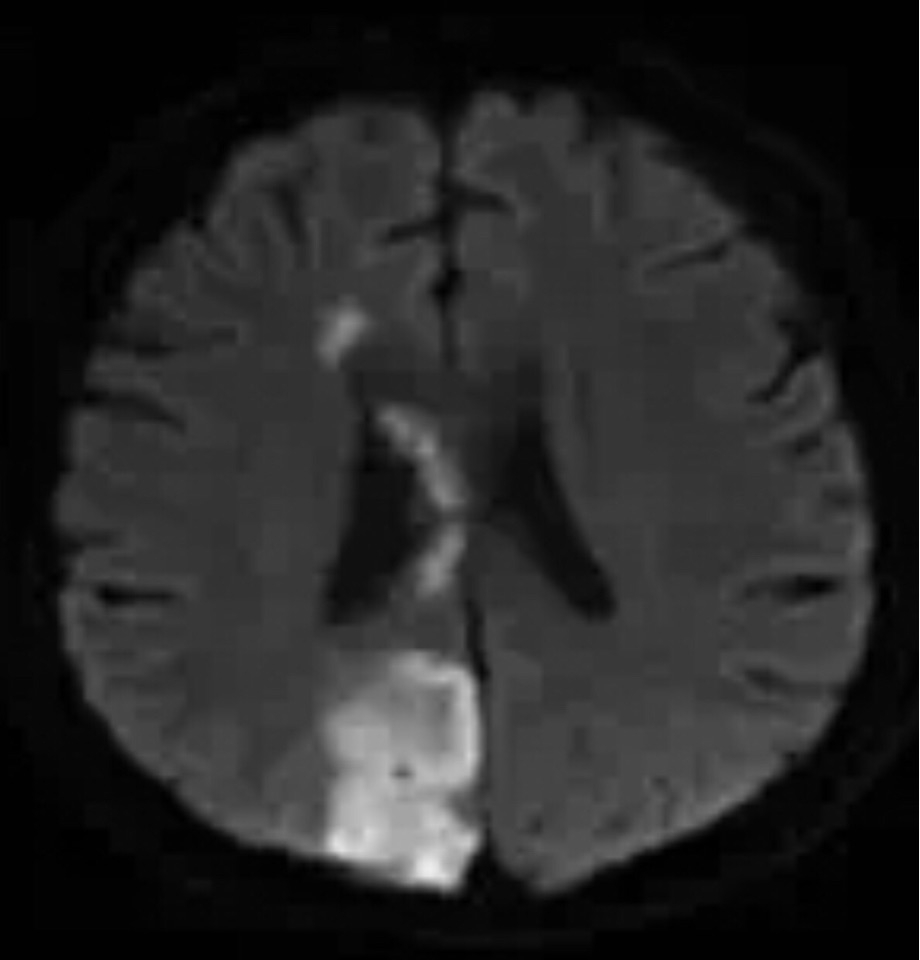

胼胝体卒中患者多有痴呆表现。头颅核磁共振检查对于确诊非常必要。患者预后取决于其基础状况。本人临床工作中仅见过一例弥漫性胼胝体梗死患者。